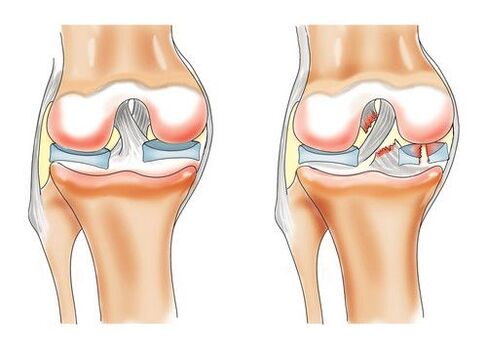

Põlveliigese gonartroosi väljakujunemist soodustavad negatiivsed protsessid hüaliinses kõhres, eelkõige halb vereringe väikestes luuveresoontes. Lümfivooluga kaasas olevate toitainete ja hapniku puudumine viib põlve välise kõhrekihi hävimiseni.

Algstaadiumis on haigust äärmiselt raske ära tunda. Liigese deformatsioon toimub aeglaselt, kuni protsessi kaasatakse klaaskeha hüaliinne kõhr. Sideme anatoomiline struktuur muutub. Tekib pilvisus, kangas pakseneb, muutub õhukeseks ja praguneb igas suunas. Patoloogia tagajärjeks võib olla kõhre täielik kadumine, mis põhjustab luukoe uute kasvu ja põlve pöördumatut kõverust.